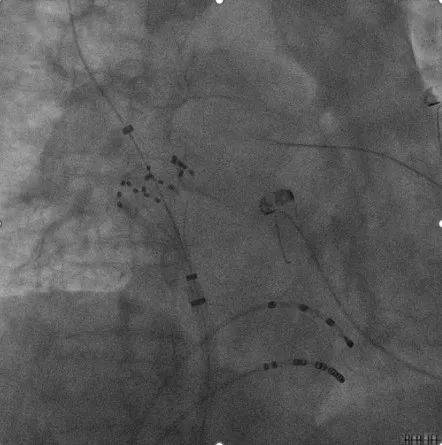

ICE引导下房间隔穿刺:

术中ICE指引导丝到上腔静脉

ICE直视下进行房间隔穿刺

穿刺后打水确认

ICE引导消融导管位置:

血流模式确认左上肺静脉

血流模式确认左下肺静脉

LSPV消融:

LSPV口内消融_ICE直视下脉冲导管以网篮形态与肺静脉贴靠

LSPV前庭消融_ICE直视下,显示脉冲导管以花瓣形态与肺静脉贴靠

ICE直视下,CP导管呈现网篮形/花瓣状贴靠在左上肺静脉,并可观察到导管进入肺静脉的深度&贴靠情况

LIPV消融:

ICE直视下,PFA导管进行左下肺静脉贴靠消融

RSPV及RIPV消融:

RSPV口内消融

RSPV前庭位置消融

RIPV口内消融

RIPV前庭位置消融